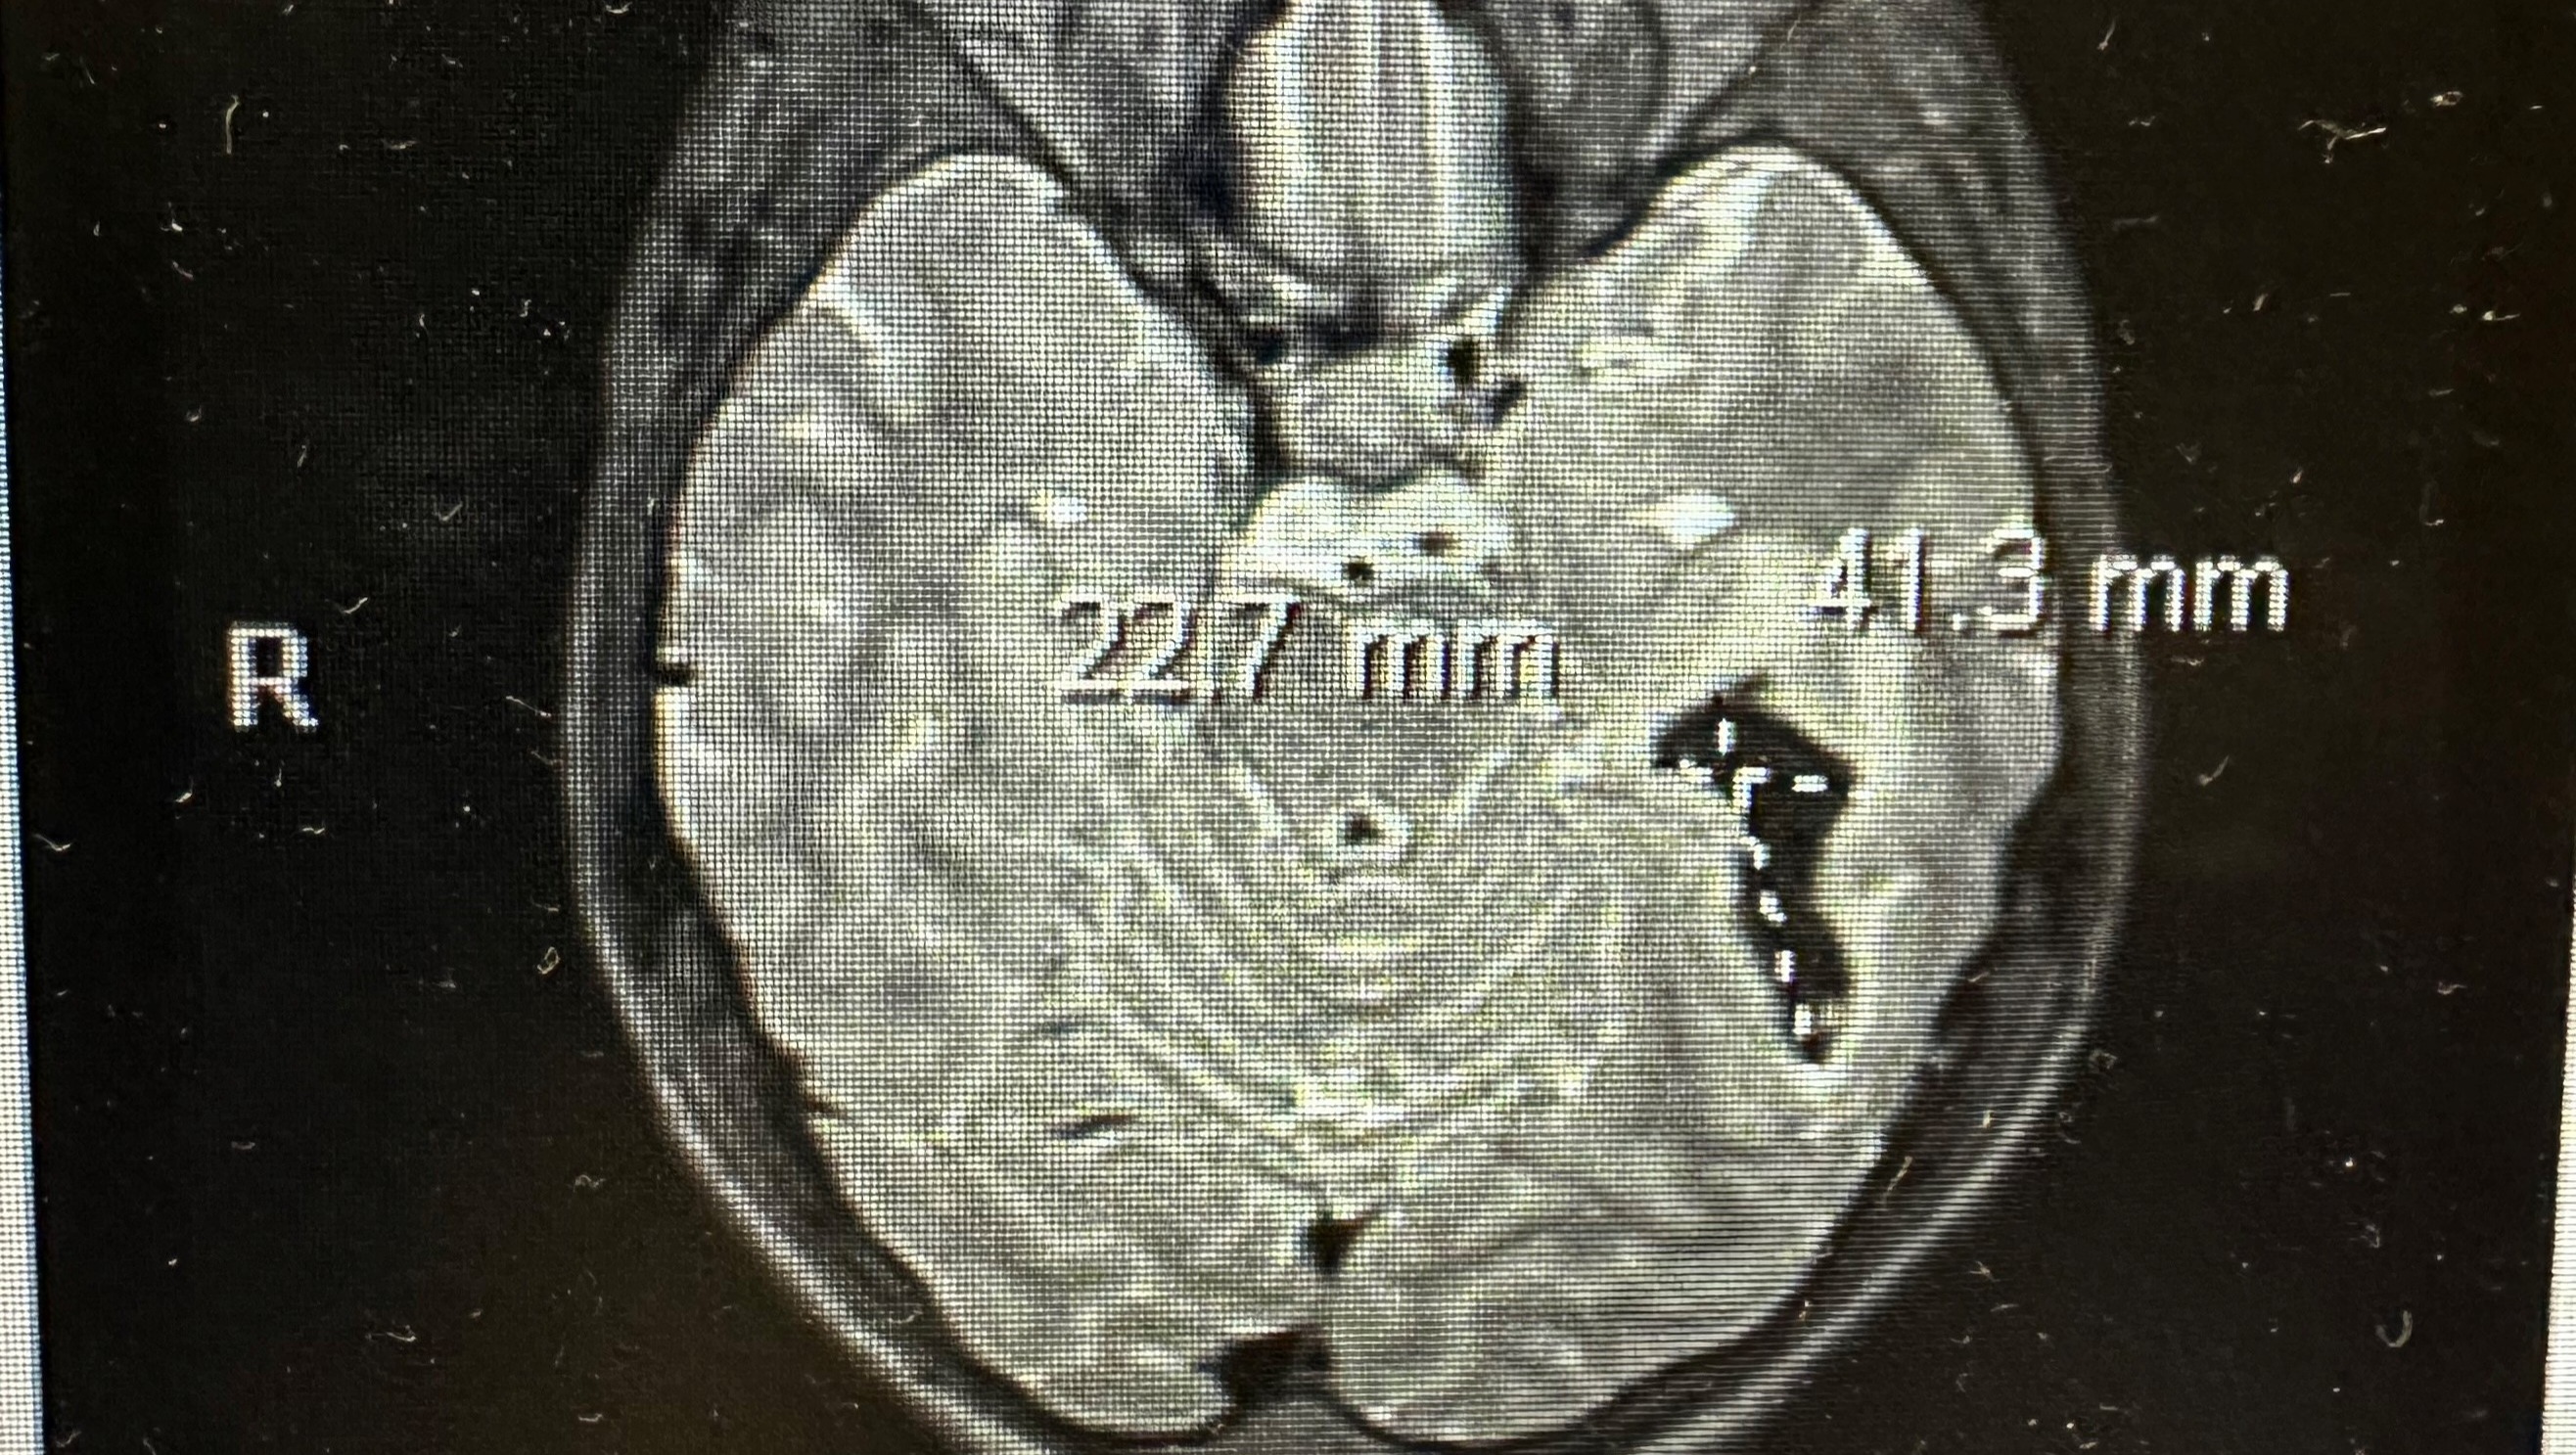

On Friday, August 23, 2024, our 13-year old son Alek, had a seizure while getting ready for school. He was rushed to the hospital in Palm Bay, FL and was incoherent. He could hardly identify me (Allie) and did not know who his dad (Mendell) was. As you can imagine, we were heartbroken and scared. They immediately began bloodwork and sent him for a brain scan. The brain scan showed that he had a brain bleed, swelling and a mass in his brain. After getting those results, we were told he needed to be airlifted to a Children's Hospital in Orlando for further testing and treatment. After discussing the transportation options, it was agreed upon that he would be transported via ambulance so one parent could travel with him as we would not be able to go in the helicopter with him. I (Allie) went with him in the ambulance and Mendell followed behind in our vehicle. Upon arrival at the Children's Hospital, they notified us that he tested positive for Rhinovirus and were looking at the scans to see what further tests needed to occur. Later that day, they took him to get an MRI and a MRA. After those tests were completed, they said that it could be a cavernous malformation or a tumor. However, it was unclear because of the swelling. They indicated we had to wait for the swelling to go down and retest. They prescribed steroids to bring the swelling down and to help the blood reabsorb in his brain. They also prescribed anti-seizure medication to prevent another seizure. Their goal for the retest was Sunday, August 25, 2024. On Saturday, August 24, 2024, Alek awoke with intense eye pressure and he was prescribed medication for that. On Sunday, August 25, 2024, they did the rescan and indicated he was stable. On Monday, August 26, 2024, they completed an angiogram. That test confirmed the mass was an Arteriovenous malformations (AVM). You can learn more about AVM's online at: https://www.mayoclinic.org/diseases-conditions/brain-avm/symptoms-causes/syc-20350260. On Thursday, August 28, 2024, they did a another scan he needed for the surgery to remove the AVM. He has started both physical therapy and occupational therapy because the bleeding and the swelling have caused some issues. He also has to see an ophthalmologist. We are now preparing for brain surgery in 2-3 weeks. Luckily, they are allowing us to go home until the surgery is scheduled. Alek will need to be home-schooled until he recovers from surgery and gets clearance to resume normal activities. This will greatly limit my ability to work.